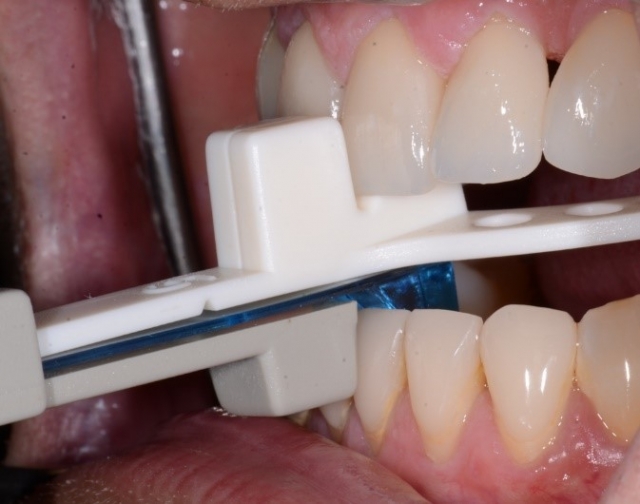

Step 1: Place the George Gauge and help the patient find a comfortable position for six to eight hours. Tighten the nob to hold the position (Fig. 4).

Step 2: Take out the George Gauge and chat with the patient for a few minutes, facilitating natural mandibular movement and forgetting our goal for those two minutes.

Step 3: Put the George Gauge with the nob tightened at the previously decided “comfortable” position back in the patient’s mouth. Ask the patient to imagine staying in this position for six to eight hours. Ask if he wants me to loosen the nob and allow him to find a new starting position.

Step 4: Repeat until the patient is comfortable with that starting position (Fig. 5).